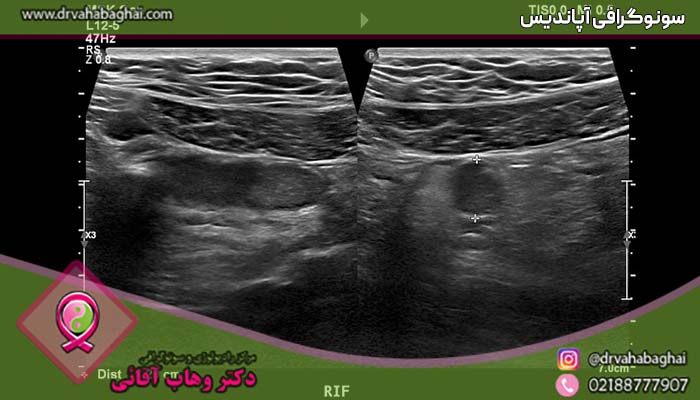

التهاب حاد آپاندیس یکی از عارضه‌های شایع اورژانسی است که به منظور جلوگیری از عوارض جدی باید به سرعت تشخیص داده شود و تحت درمان قرار گیرد. آپاندیس یک زائده کوچک و انگشتی شکل است که از ابتدای روده بزرگ منشعب می‌شود و انتهای آن بسته است. افرادی که به التهاب آپاندیس دچار می‌شوند باید سریعاً توسط پزشک معاینه شوند و سونوگرافی آپاندیس در آن‌ها به منظور تشخیص میزان التهاب یا پارگی احتمالی آن انجام شود.